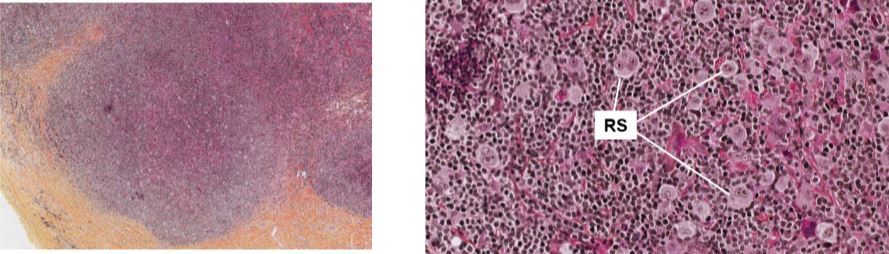

Lymphome de Hodgkin de type scléro-nodulaire avec cellules Reed-Sternburg

ce quon voit ici c’est un ganglion lymphatique

Lymphome de Hodgkin

gauche: nodule riche en cellule tumorale et lymphocyte qui est entouré de bcp de tissus conjonctif

droite: cytoplasme abondant, grosse cellules multinucléaire , volumineux nucléoles ce sont les cellules de Reed-Sternburg